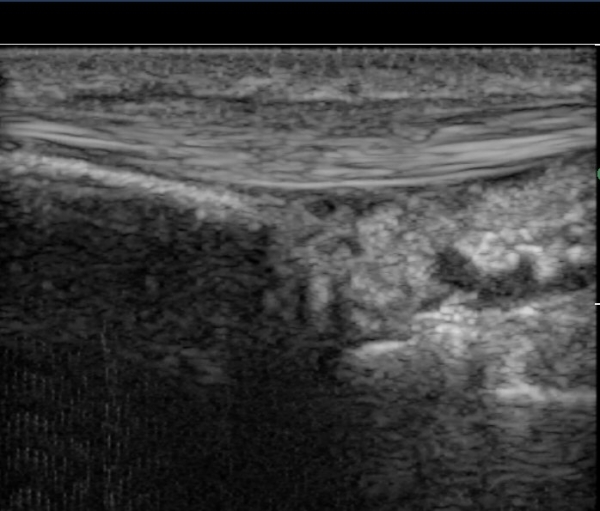

´Ü¹«Áö½ÅÀü°Ç(EPB) Á¾´Ü¸é°Ë»ç¿¡¼­ °ÇÀÇ ºÎÁ¾ ¹×°ÇÁÖÀ§ ¼ö¾×Àú·ù°¡ °üÂûµÊ(»çÁø 4)

ÃÊÀ½ÆÄ À¯µµÇÏ ÁÖ»çÄ¡·á »çÁø¿¡¼­ ÁÖ»ç ¹Ù´ÃÀÌ °ÇÁÖÀ§ ºÎÁ¾ ºÎÀ§¿¡ Á¤È®È÷ À§Ä¡ÇÔ(»çÁø 5, ÷ºÎÆÄÀÏ)